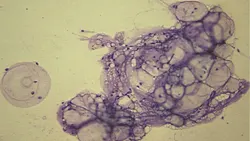

Q • What types of nonneoplastic masses are found in dogs and cats**?A • Common nonneoplastic masses include sebaceous hyperplasia/adenoma and follicular cysts. Follicular cysts consist of thick aggregates of keratinaceous debris and mature, keratinized, anucleated squamous epithelial cells (Figure 2**).